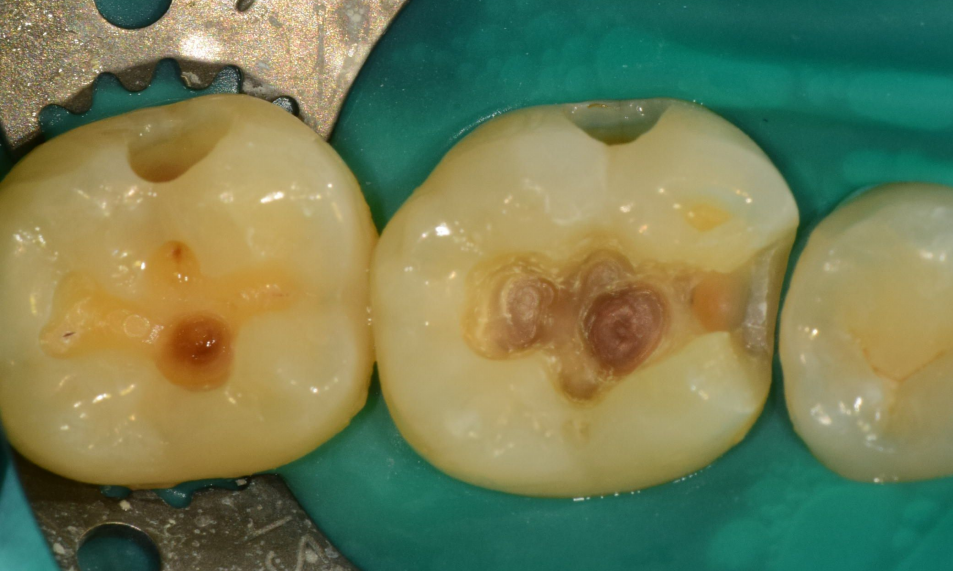

이로운치과는 근관치료, 충치치료 시 러버댐을 사용한 치아 격리 원칙을 최대한 지킵니다.

복합레진을 이용한 수복치료 시 치아 본연의 외형을 재현하려 노력합니다.